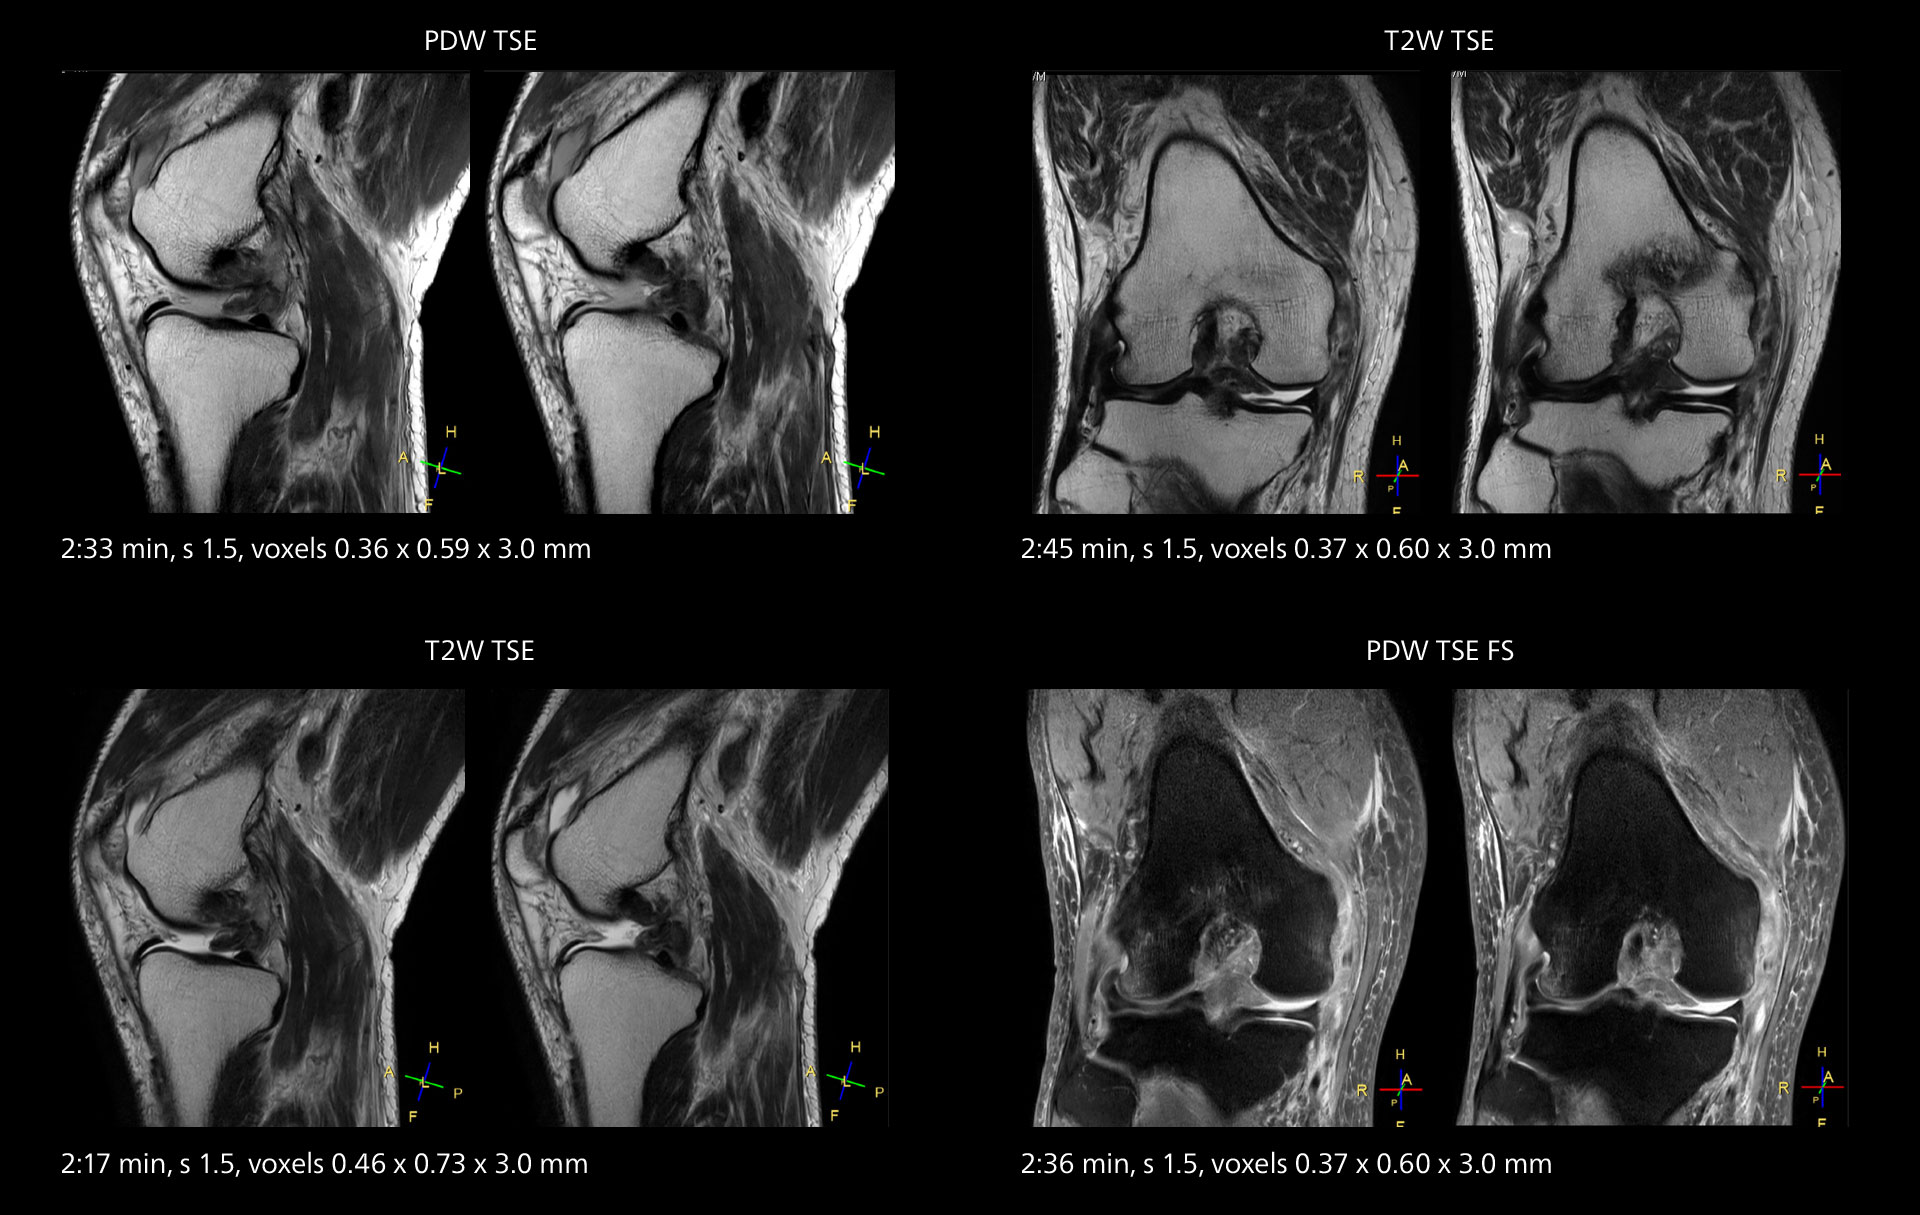

MRI of the knee

Images showing a posterior cruciate ligament (PCL) tear, a detached medial collateral ligament (MCL) on the tibial side and an intact anterior cruciate ligament (ACL). SmartPath to Elition X helped reduce scan time compared to previous imaging while maintaining resolution.

An example of increased imaging speed is in knee studies. “There is a definite scan time reduction for T2* mFFE and proton density TSE – both of these sequences benefit from much shorter repetition times,” he reports.

Overall, imaging time per sequence has been reduced since the Elition X upgrade. This can help reduce the risk of patient movement and the need for rescans.

“As our hospital has many elderly patients, we consider it important to obtain high-quality data in a short time,” Dr. Makuuchi says. “Shorter imaging times are also useful for accepting emergency patients, because faster emergency studies have a reduced impact on the daily examinations schedule. In emergency cases it is also important that high quality images are obtained in a short time.”